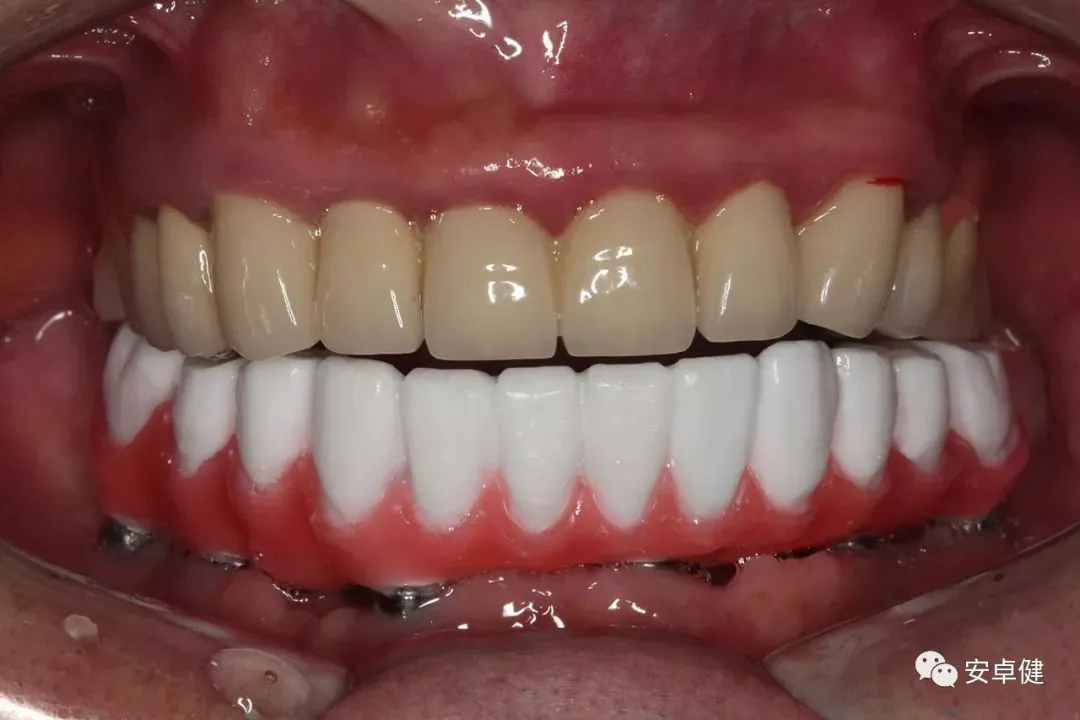

戴最终修复体正面咬合照

戴牙后4个月复诊正面咬合照

最终修复后8个月

戴牙后8个月复诊正面咬合照

• 随访可见患者口腔卫生状况可,牙龈无红肿;

• 下颌修复体状态良好,无修复体机械并发症;

• 种植体基台稳定性良好,无松动;

• 种植体无松动,周围无红肿、溢脓及疼痛表现;

• 正中、前伸及侧方咬合检查可见咬合印记分布均匀,咬合关系良好;

• 患者反映日常使用良好,舒适性佳,满意度高。